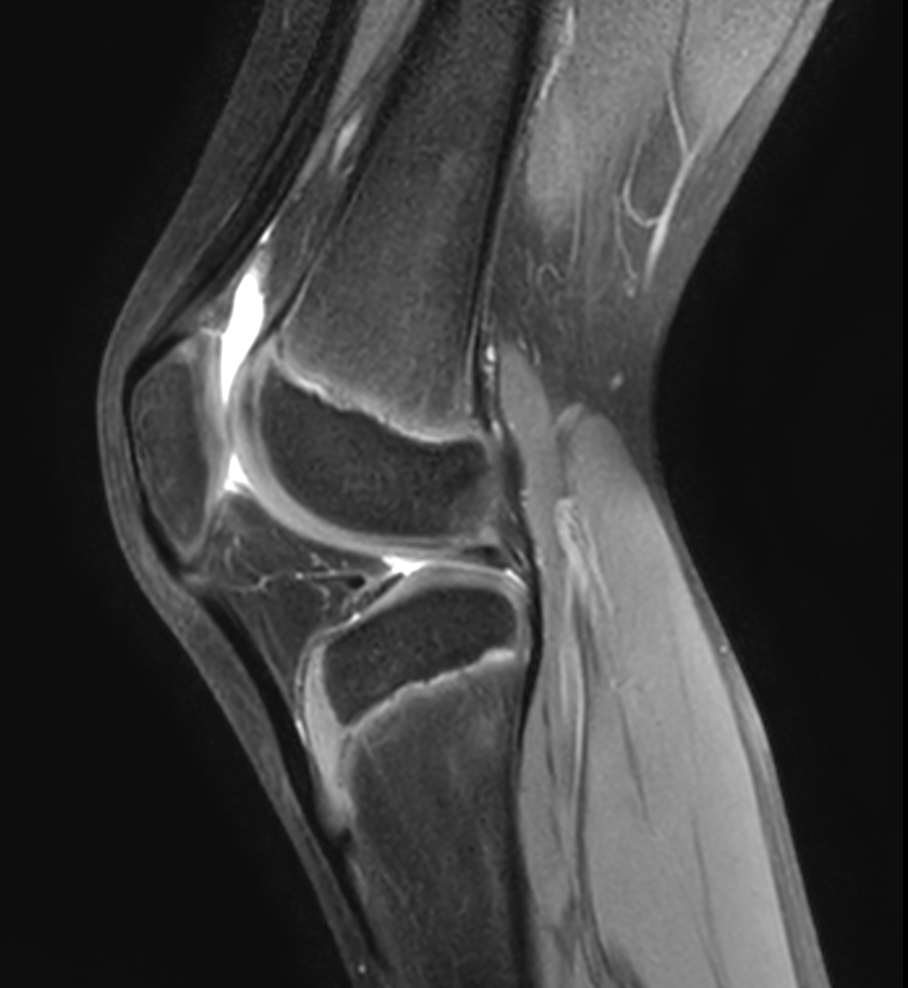

Sagittal PDw SPAIR

Sagittal 3D VIEW PDw SPAIR